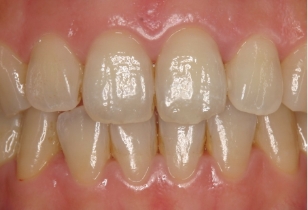

従来の矯正と当院の矯正の術後変化の比較

従来の矯正(ジナド先生の報告)と当院の矯正の調査法2)は少し異なるため、それぞれの保定終了時のスコアまたは指数を100%として、その後の変化を比較しました。

これによると当院の治療後の歯並びの変化は、従来の矯正に比べ変化が非常に少ない事が分ります。つまり当院の矯正治療は、従来の矯正治療に比べ大変に安定していることが分かります。

このように当院の矯正治療の術後経過は、従来の矯正に比べ安定していることが分かります。

しかし当院の歯並びもよく観察すると、少しは指数が増加、つまり多少は歯並びが悪くなっていることが分かります。実はこれは自然な歯並びの変化と同じものである事がわかりました。つまり歯並びは下の写真が示すように矯正をしてない人でも、変化するのです。その自然な変化をリトル教授のお仲間のシンクレア先生が報告しており、そのデータを追加したのが下の図です(グラフのグレー)。これをみると元々綺麗な歯並びだったものも7年経過するとリトルの指数が35%も増加していることが分かります。

当院のリトルの指数の増加は5年で31.9%でしたが、今回の調査で、伊藤矯正歯科医院の治療後の変化は自然な変化と「統計的に差はない」という結果が出ました。